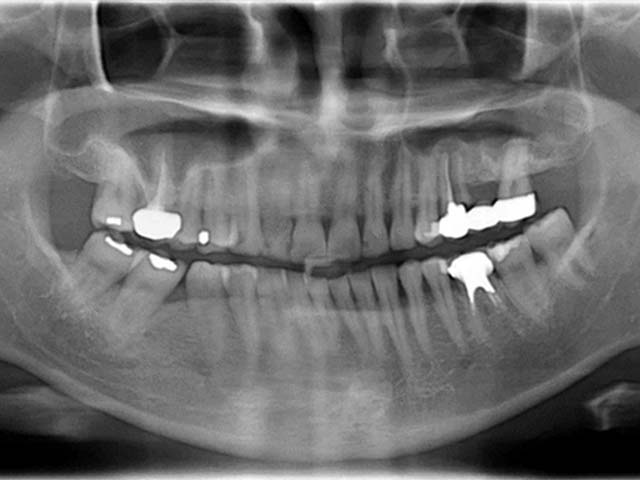

鼻竇增高術(側窗) 首頁 案例分享 人工植牙 鼻竇增高術(側窗) 鼻竇增高術(側窗) 製作多年的牙橋,牙根斷裂,發炎 鼻竇增高術 側面開窗 抬高鼻竇 鼻竇增高術 置入骨粉 覆蓋再生膜,保護骨粉 術後追蹤,傷口良好 裝戴正式假牙 完成 8年追蹤 左上牙根斷裂 植牙重建 九年追蹤